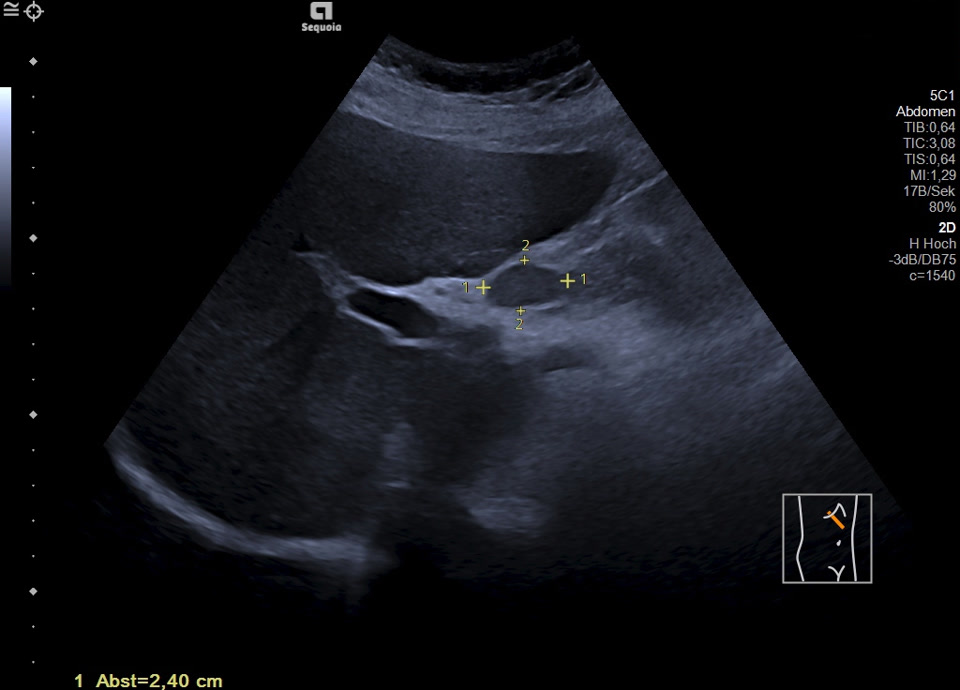

Malignitätsuspekte Raumforderung retroperitoneal und die A. mesenterica superior ummauernd (siehe Markierung), sonographische Punktion ergibt ein Non-Hodgkin Lymphom der B-Zell-Reihe (anaplastische Morphologie)

Malignitätsuspekte Raumforderung retroperitoneal und die A. mesenterica superior ummauernd, sonographische Punktion ergibt ein Non-Hodgkin Lymphom der B-Zell-Reihe (anaplastische Morphologie)